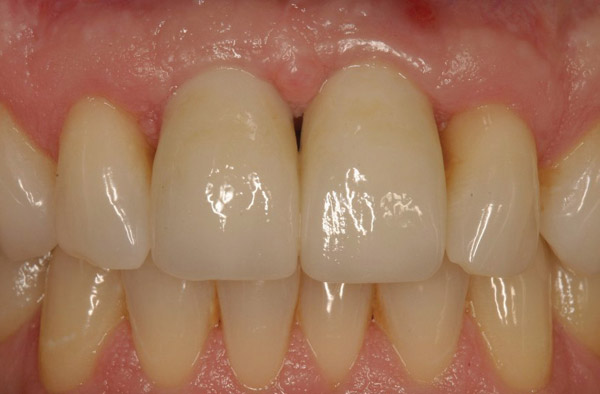

Figure 19  The post-implantation and post-restoration view shows esthetically pleasing, symmetric crowns and mucosal contours, with the Nos. 7 and 10 implant prostheses blending in imperceptibly with the natural dentition. Restoration courtesy of Dr. Jeffrey Warren.

Figure 19